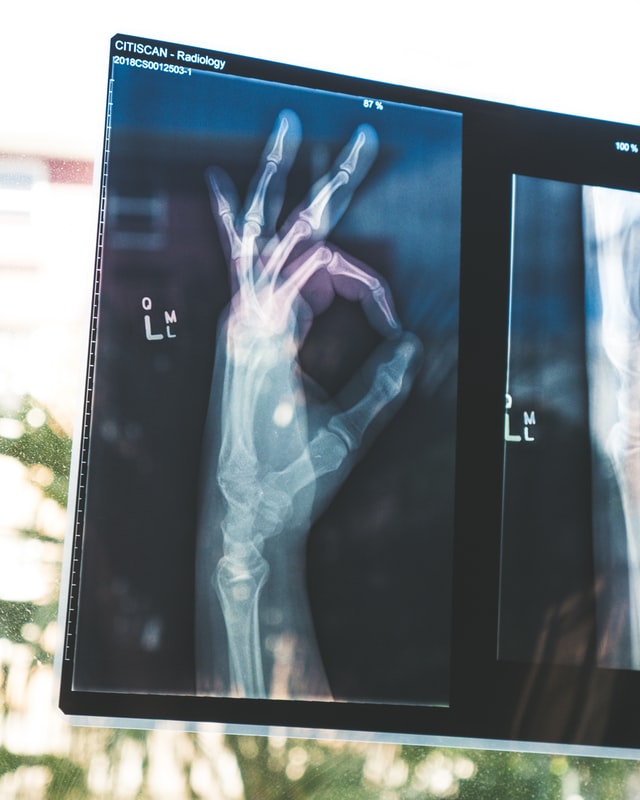

Handchirurgie

Unsere Hände sind täglich im Einsatz – sie ermöglichen uns zu greifen, zu fühlen, zu schreiben, zu arbeiten. Wenn ihre Funktion durch Verletzungen, Verschleißerkrankungen oder Nerveneinengungen gestört ist, bedeutet das oft eine erhebliche Einschränkung im Alltag. In unserer Praxis in Berlin Mitte bieten wir Ihnen eine spezialisierte handchirurgische Behandlung auf höchstem medizinischem Niveau.

Die Handchirurgie erfordert besondere Präzision, umfassende Erfahrung und viel Feingefühl. Unser Team aus erfahrenen Fachärztinnen und Fachärzten versorgt Sie individuell, kompetent und mit modernen schonenden Verfahren – in vielen Fällen ambulant und ohne stationären Aufenthalt.